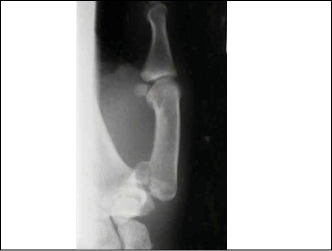

Bennett fractures are defined as fractures of the first metacarpal of the hand, with the fracture line extending from the base of the metacarpal (MC) to the CMC joint.16 (See Figure 4.) Bennett fractures are the most common thumb MC fractures. Involvement of the CMC makes this fracture unstable. The break occurs obliquely through the intra-articular surface of the base of the metacarpal. The most common mechanism of injury is axial loading of a flexed metacarpal. A Bennett fracture should be suspected clinically whenever there is a mechanism of punching a solid object or falling onto the thumb. Pain and focal tenderness at the base of the thumb are typical. A quick way to recognize a Bennett fracture radiologically is that a small fracture fragment stays with the carpals. When a Bennett fracture occurs, the proximal fragment is maintained in anatomic position due to strong attachment of the anterior oblique ligament to the tubercle of the trapezium. The distal fragment, however, which is attached to other tendons and ligaments of the hand, is pulled away from the joint by the forces exerted by adductor pollicis (which pulls the metacarpal head toward the palm) and the abductor pollicis longus (which subluxates the base in a dorsal, radial, and proximal direction).16

Figure 4. Bennett Fracture Radiograph